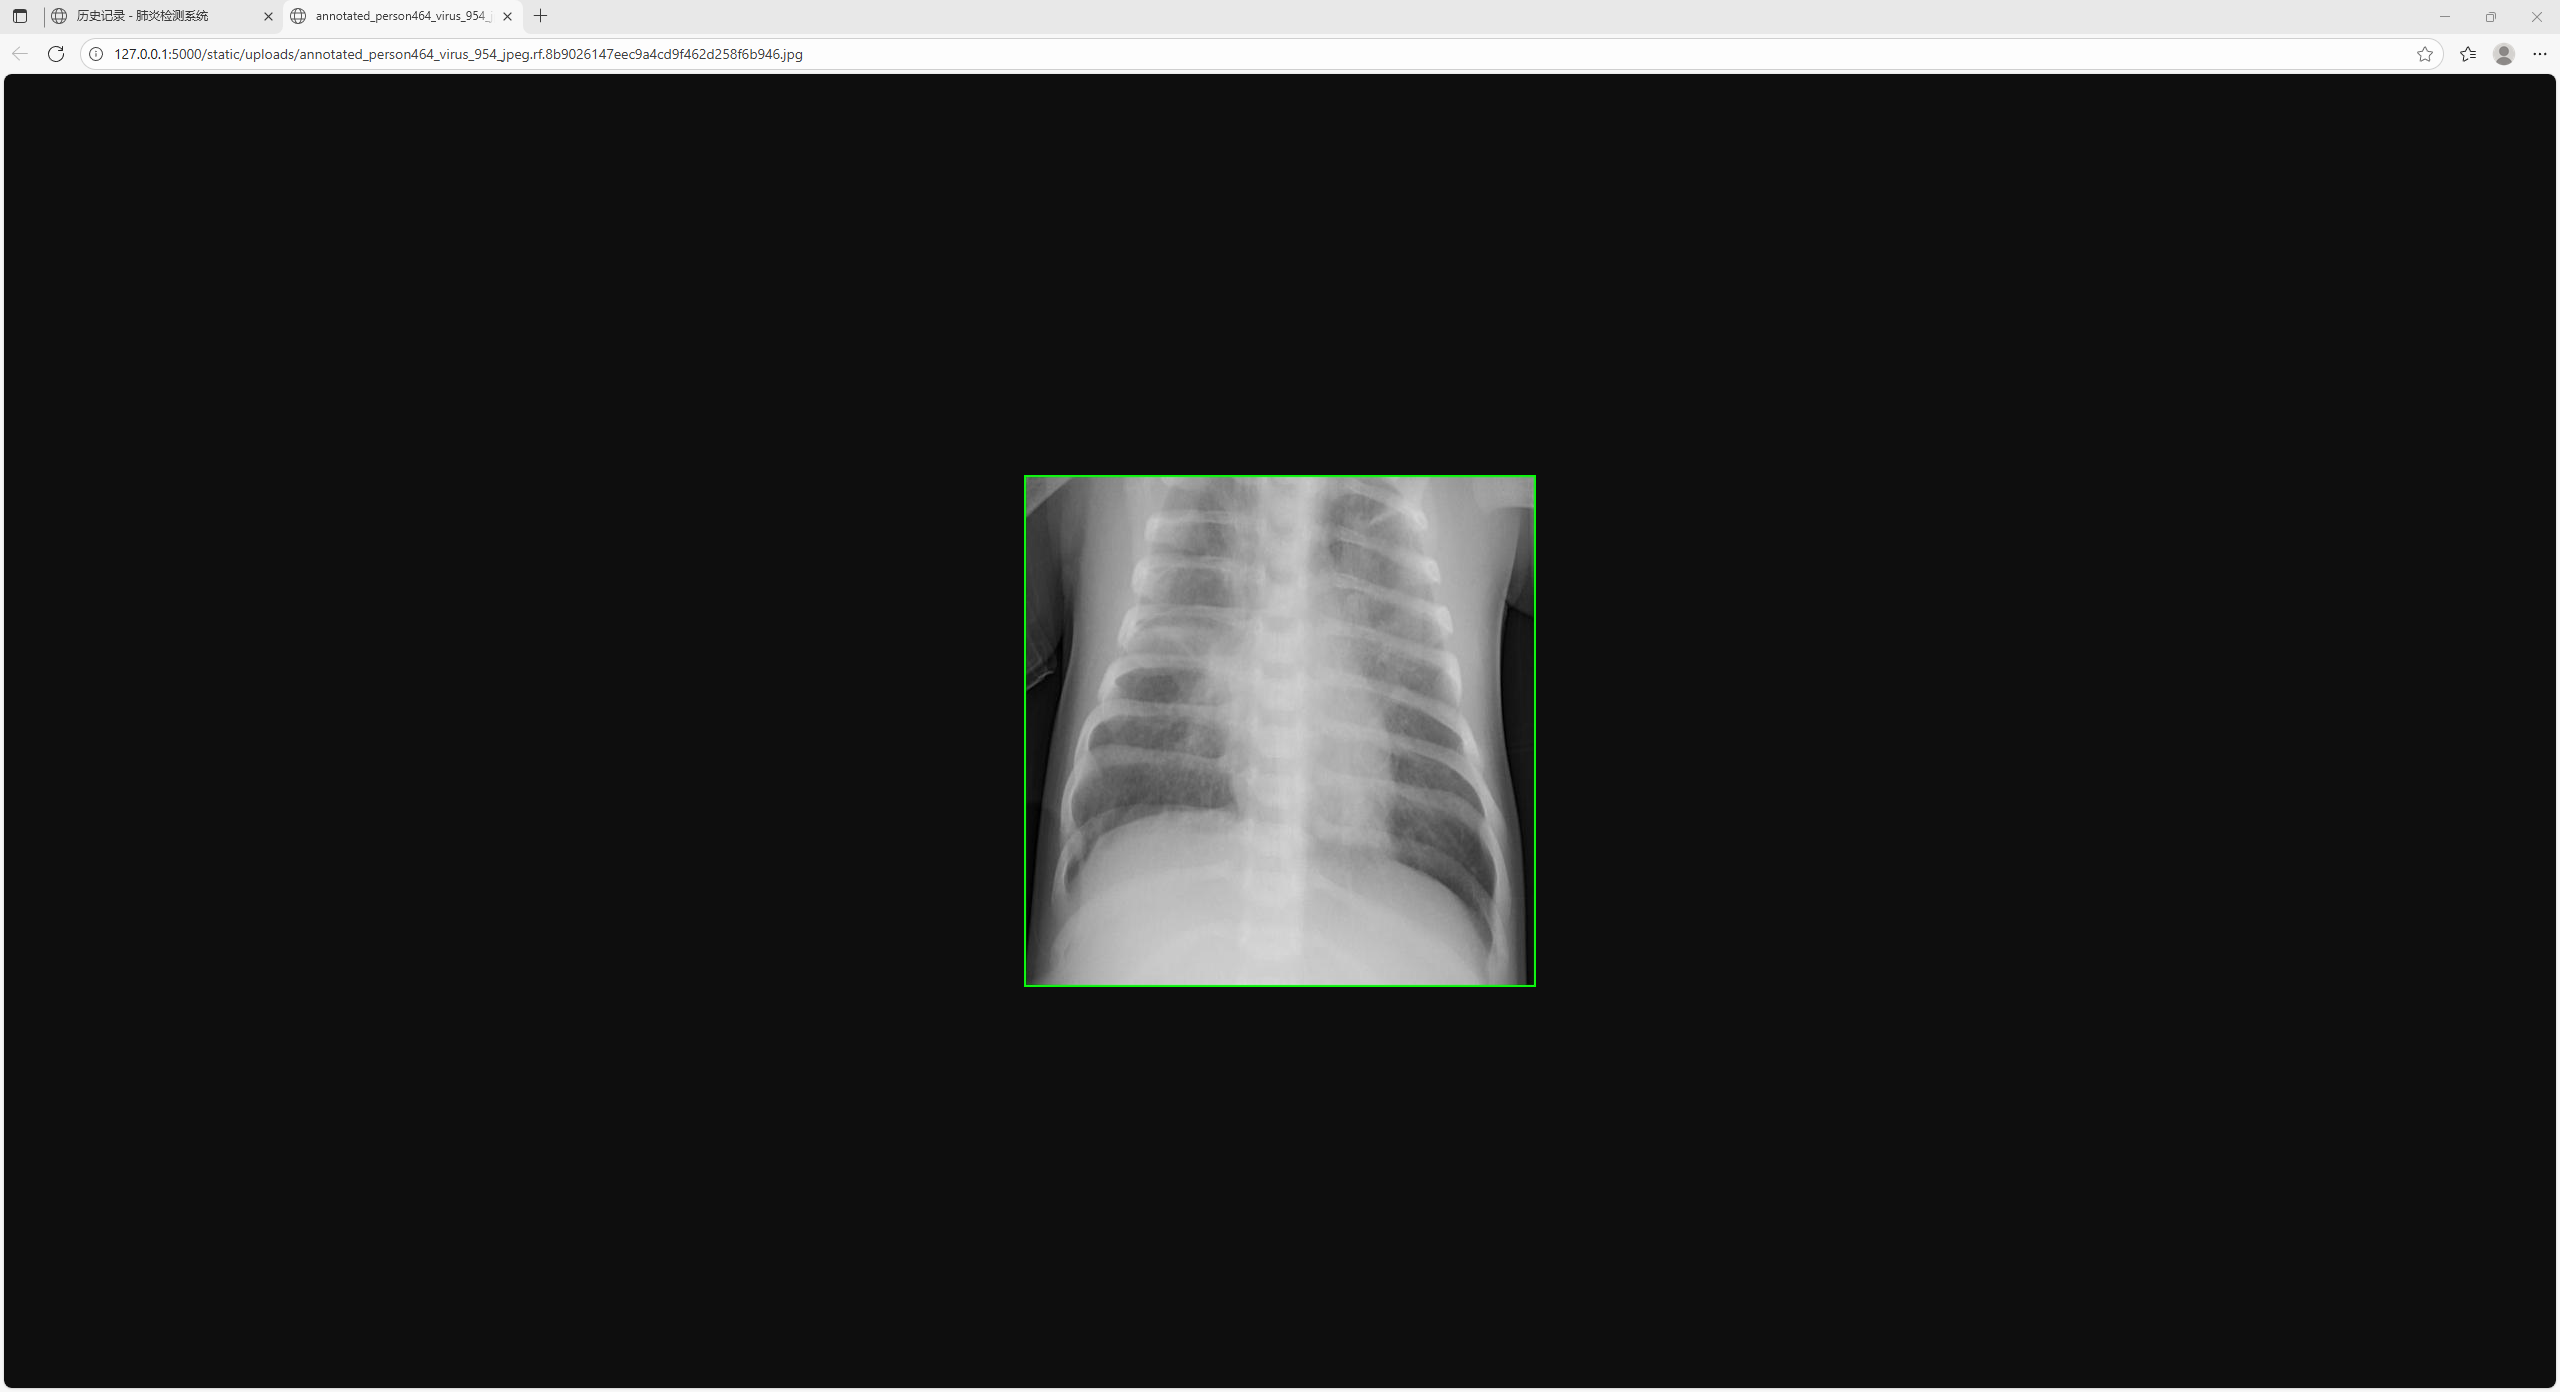

图26 检测历史记录

图27 历史记录图片放大